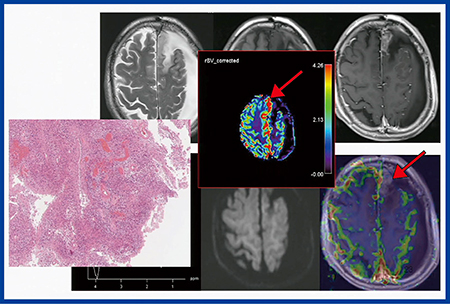

膠芽腫症例(70歳代,男性)の摘出術後フォローアップで,術後約1年で再発が疑われる所見が認められた。MRI装置のコンソール上のperfusion解析では,再発と思われる病巣にCBVの上昇が認められず放射線壊死(radiation necrosis)と診断してしまう可能性があったが(図2右下↓),Olea Sphereで漏出補正を行うと高信号を示し(図2中央↓),再発であることが示唆された。この腫瘍は摘出術が施行され,再発腫瘍であることが確認されたが,その3か月後に,さらにもう1つ腫瘍を再発した。この際も,通常のperfusion解析では低CBVとして示され(図3 b→),漏出補正を行うと高いCBVを示した(図3 c→)。これは,Ktrans(図3 d→)が高値を示すことからわかるように,造影剤が血管外に漏出しているためである。このように腫瘍のperfusion MRIでは,漏出補正をしなければ正しいデータを得ることができないので注意が必要である。

図2 膠芽腫再発症例(70歳代,男性)

perfusion MRIでOlea Sphereの漏出補正により再発であることが示唆された。